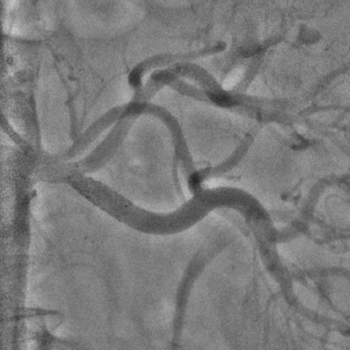

Бифуркационное стентирование почечной артерии

Ангиографическое исследование аорты и селективная ангиография сосудов почек выявило критический стеноз a. segmenti inferioris и короткую a. renalis sinistra

Операторы: Андрей Мальцев, Дмитрий Лебедев